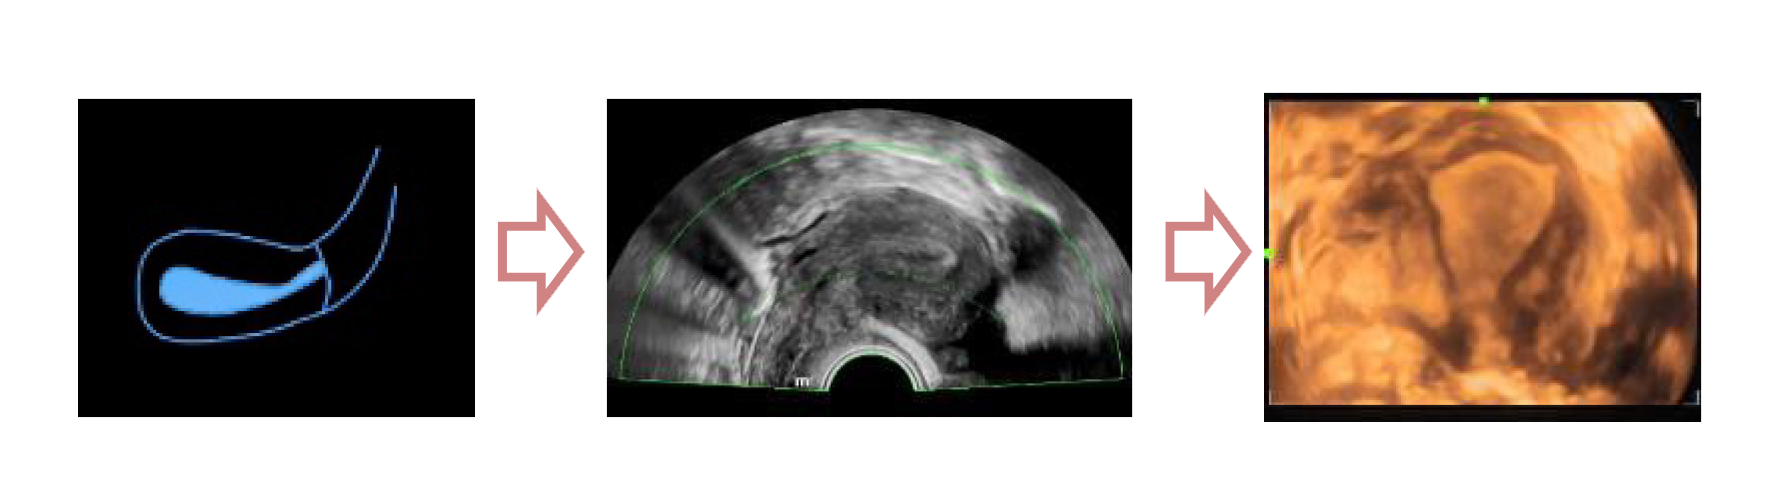

Полноценное интеллектуальное решение для диагностики матки, для легкой и быстрой оценки эндометрия

- Автоматическое распознавание матки

- Автоматическая подстройка зоны интереса и положения до оптимального

- Автоматический объемный рендеринг эндометрия